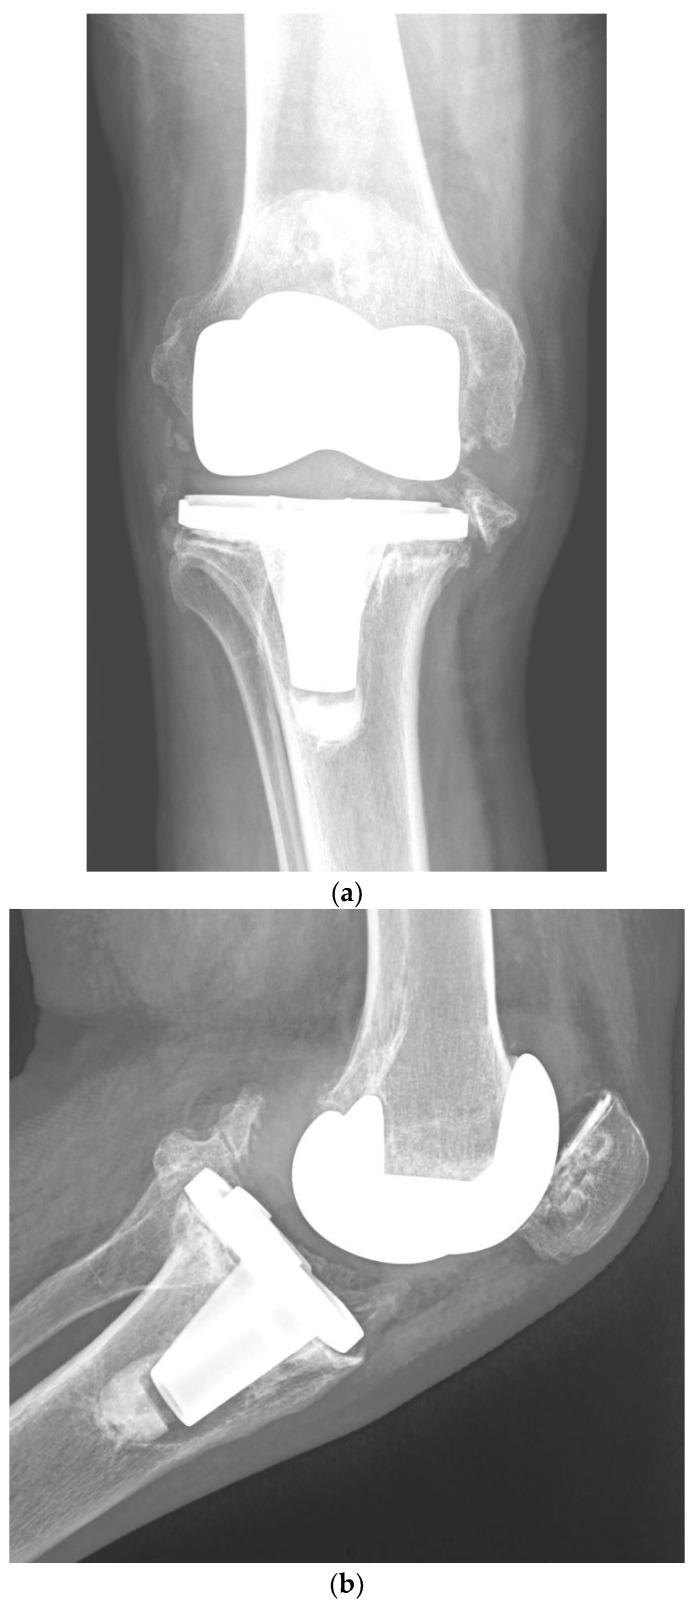

Risk Factors for Periprosthetic Joint Infection after Primary Total Knee Arthroplasty.

Periprosthetic joint infection (PJI) is a major adverse event of primary total knee arthroplasty (TKA) from the patient's perspective, and it is also costly for health care systems. In 2010, the reported incidence of PJI in the first 2 years after TKA was 1.55%, with an incidence of 0.46% between the second and tenth year. In 2022, it has been published that 1.41% of individuals require revision TKA for PJI. The following risk factors have been related to an increased risk of PJI: male sex, younger age, type II diabetes, obesity class II, hypertension, hypoalbuminemia, preoperative nutritional status as indicated by prognostic nutritional index (PNI) and body mass index, rheumatoid arthritis, post-traumatic osteoarthritis, intra-articular injections prior to TKA, previous multi-ligament knee surgery, previous steroid therapy, current tobacco use, procedure type (bilateral), length of stay over 35 days, patellar resurfacing, prolonged operative time, use of blood transfusions, higher glucose variability in the postoperative phase, and discharge to convalescent care. Other reported independent risk factors for PJI (in diminishing order of importance) are congestive heart failure, chronic pulmonary illness, preoperative anemia, depression, renal illness, pulmonary circulation disorders, psychoses, metastatic tumor, peripheral vascular illness, and valvular illness. Preoperative intravenous tranexamic acid has been reported to diminish the risk of delayed PJI. Knowing the risk factors for PJI after TKA, especially those that are avoidable or controllable, is critical to minimizing (ideally preventing) this complication. These risk factors are outlined in this article.